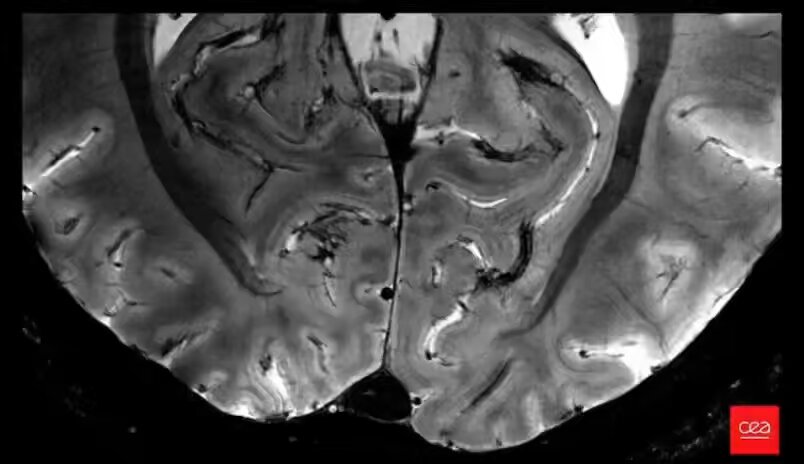

Emmanuel Macron, président de la République, a tweeté son émerveillement face à une innovation impressionnante en matière de science médicale. Selon le tweet qu’il a partagé, le CEA (Commissariat à l’énergie atomique et aux énergies alternatives) a réussi à produire l’image la plus précise du cerveau jamais obtenue, grâce à son scanner par résonance magnétique, le plus puissant au monde.

Selon les informations provenant du tweet présidentiel, cette image du cerveau a été réalisée grâce à l’utilisation d’une technologie de pointe, à savoir le scanner par résonance magnétique (IRM) du CEA, qui est le plus performant du monde. C’est signe que l’investissement dans l’innovation technologique se révèle bénéfique pour la santé publique.

This is the most precise image of the brain ever obtained, thanks to the CEA's MRI scanner, the most powerful in the world.